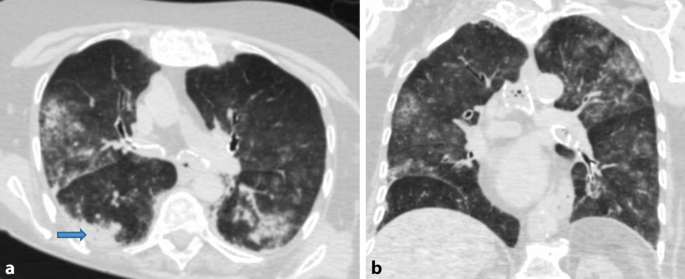

Having pneumonia from a. In diagnosis chest computed tomography CT manifestations can supplement parts of limitations of real-time reverse transcription polymerase chain reaction RT-PCR assay. Persistent Viral Presence Determines the Clinical Course of the Disease in COVID-19.

This is due to abundant ACE2 receptor expression in the lung parenchyma specifically on the acinar side of lung epithelial cells pneumocytes within the alveolar spaces allowing virus entry Fig 1 5. Dhypoxmie certains patients Covid-19 prsentent une gne respiratoire plus ou moins. 20200627 To compare the chest computed tomography CT findings of coronavirus disease 2019 COVID-19 to other non-COVID viral pneumonia.